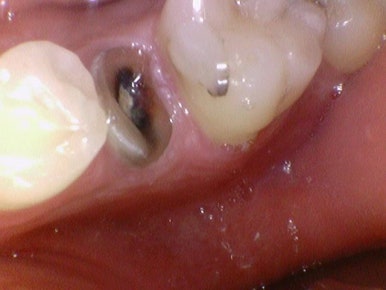

지르코니아 크라운 치료 전 후

지르코니아 크라운 치료 전후